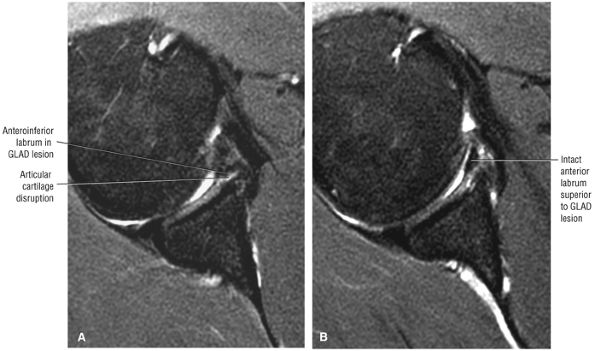

-

The imaging reference to hypertrophy of the coracoacromial ligament correlates with fraying or fragmentation of the ligament in association with impingement.

A symptomatic os acromiale is associated with marrow edema on either side of the synchondrosis.

Degenerative tendinopathy or intrinsic tendon degeneration associated with eccentric tensile overload may be the primary pathology in impingement.